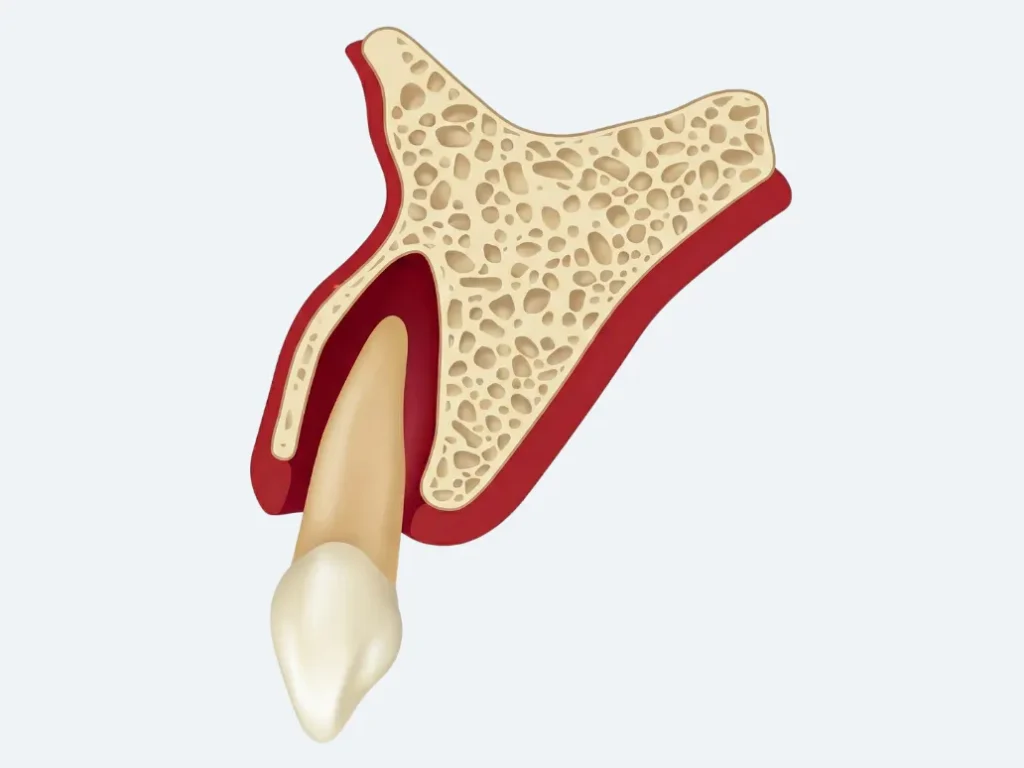

Zwichnięcie zęba to poważny uraz stomatologiczny, przy którym ząb przemieszcza się w obrębie zębodołu, jednak nadal utrzymuje częściowy kontakt z kością wyrostka zębodołowego. W przeciwieństwie do wybicia zęba (avulsji), gdzie dochodzi do całkowitej utraty kontaktu zęba z zębodołem, przy zwichnięciu struktury podporowe zęba pozostają częściowo zachowane – choć często poważnie uszkodzone.

- Zwichnięcie boczne (lateral luxation) – przemieszczenie zęba w kierunku wargowym lub podniebiennym, korzeń często „zablokowany” w złamanej kości

- Wysunięcie zęba (extrusive luxation) – częściowe wysunięcie zęba z zębodołu w kierunku osiowym

- Wbicie zęba głębiej (intrusive luxation) – wtłoczenie zęba w kość wyrostka zębodołowego

U dzieci z uzębieniem mlecznym kość wyrostka zębodołowego jest znacznie bardziej miękka i podatna na odkształcenia. Dlatego urazy mechaniczne u maluchów częściej prowadzą do zwichnięć i przemieszczeń niż do złamań koron – odwrotnie niż u dorosłych.